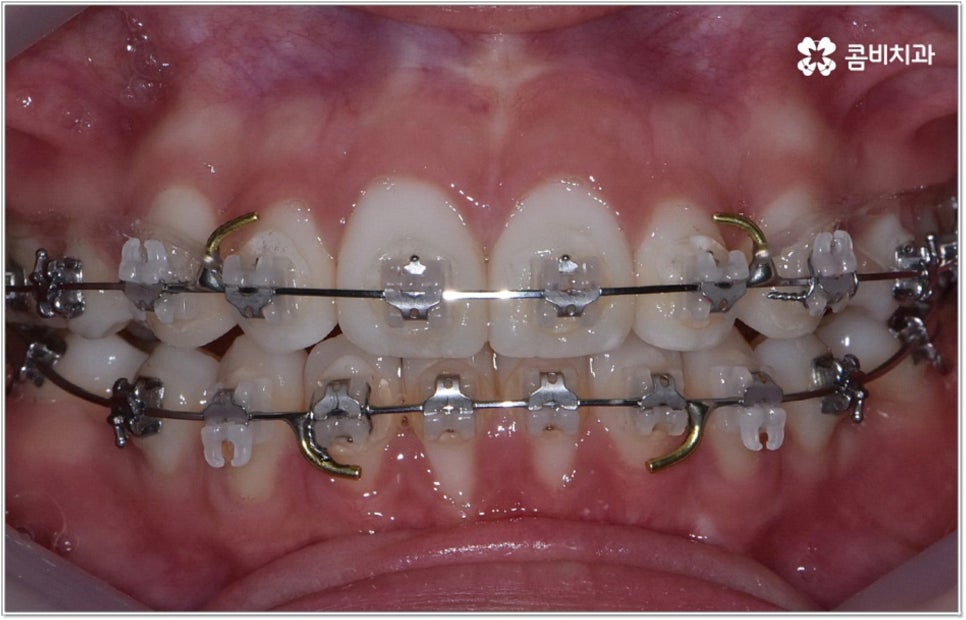

청소년기는 교우 관계에 영향을 많이 받고 외모에 민감할 때라 교정기에 대한 반감이 있을 수 있으나 바로 이때가 치아 이동에 있어 매우 중요한 시기이므로 제대로 이해할 수 있도록 차근차근 설명해 줄 필요가 있는데요. 12~15세 사이, 즉 초등학교 고학년에서 중학교 저학년 사이가 유치에서 영구치로 거의 다 교체되고 잇몸뼈가 계속해서 성장하는 나이이기 때문에 상악과 하악의 균형잡힌 발달을 유도하면서 부정교합을 바로잡고 치열을 가지런하게 만드는데 보다 빠르고 효율적인 만큼 가능하다면 이 시기를 놓치지 않는게 중요한 거예요. 물론 성인분들도 상황에 맞게 교정 치료를 진행할 수 있지만 부정교합의 종류와 정도에 따라 성장기 교정 치료를 진행하는 것이 좀 더 나은 케이스가 있으니 아이의 치열에 관심을 가지고 정확하게 알아보시는 것이 도움이 될 수 있습니다.

무리하지 않고 돌출입치아교정 과정을 진행하기 위해서는 먼저 꼼꼼한 검진 및 분석에 따른 철저한 맞춤 치료 계획 수립이 중요하다고 할 수 있는데요. 특히 3D CT 및 모르페우스 시스템을 통해 현재 아이의 치열이나 연조직, 상하악 관계 등을 자세히 살펴보고 안모 분석 후 교정 치료가 끝난 예상 모습을 시뮬레이션해서 보여주면 환아의 흥미를 유발하고 앞으로 진행될 사항에 대한 이해도를 높여줄 수 있어 긍정적인 영향을 줄 수 있으니 정밀 검진 장비를 갖추고 숙련된 의료진이 치료하는 치과에서 돌출입치아교정 과정을 진행하시길 권유드리고 있어요.

성장기 교정의 경우 턱성장 추이에 맞추어 섬세하게 치아 이동 속도를 결정해야 하므로 구강 검진 외에도 성장판 검진 등을 통해 아이의 전반적인 발달 상황에 대한 유기적인 이해를 바탕으로 치료를 하는 경험 많은 담당의 선생님께 시술을 맡기실 필요가 있습니다. 또한 이렇게 뛰어난 노하우와 기술력을 갖춘 것 뿐 아니라 사전 상담, 전 교정 과정 그리고 사후 관리에 이르기까지 지속적인 소통을 통해 불편한 점이 없는지 세심하게 살피고 개개인의 상황 및 구강 건강을 전체적으로 신경써서 케어해 주는 의료진과 함께 한다면 환아 뿐 아니라 부모님의 입장에서도 더욱 안심이 되고 좋을 거예요.